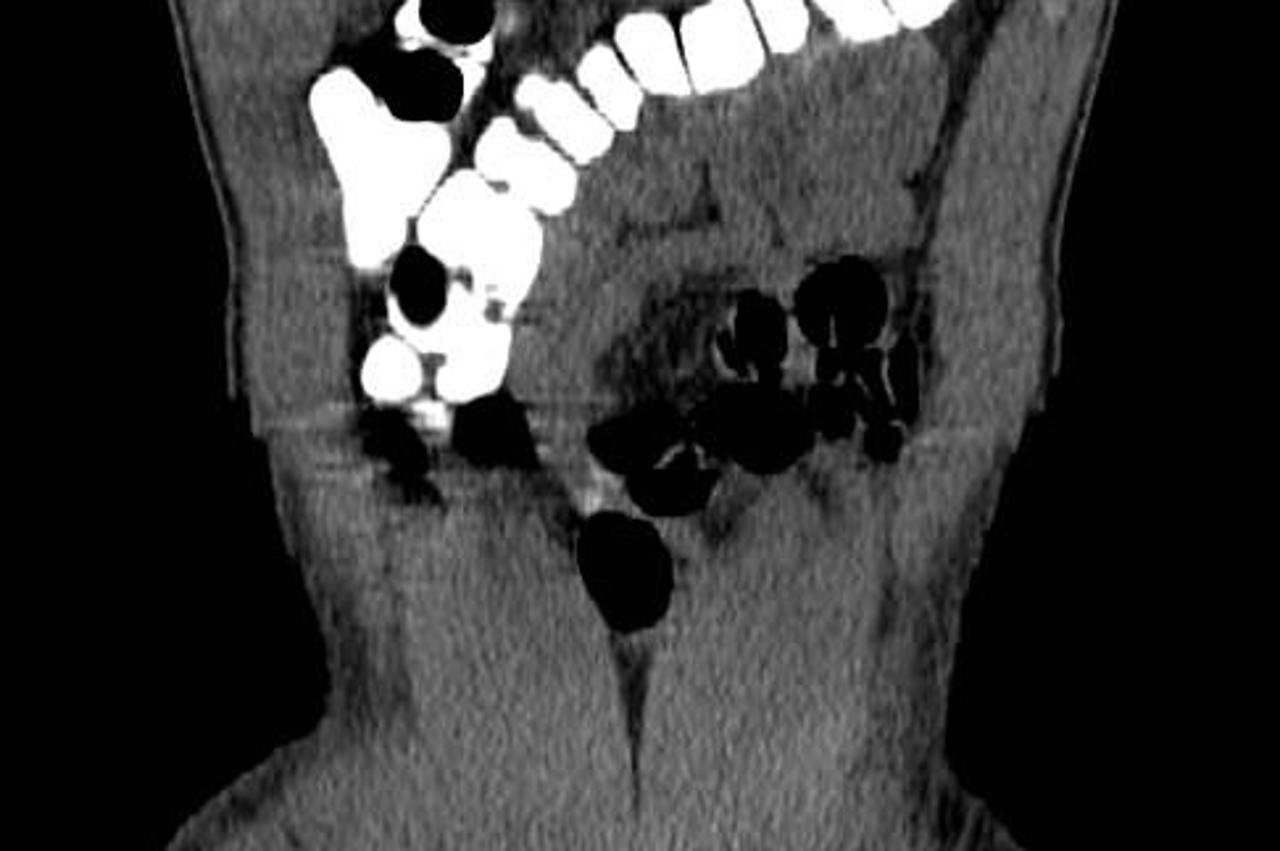

U Beogradu otkrivena 'mula': U želucu imao pola kg kokaina

Više od pola kilograma kokaina pokušao je prokrijumčariti u želucu jedan Srbin u beogradskoj zračnoj luci Nikole Tesle.

Muškarac je uhićen prekjučer na aerodromu, a ova je 'mula' u Srbiju stigla iz Mozambika, a ne Južne Amerike kao što je to uobičajeno, piše Blic.

Krijumčar je nakon uhićenja odvezen u bolnicu te još izbacuje paketiće droge koje je progutao.